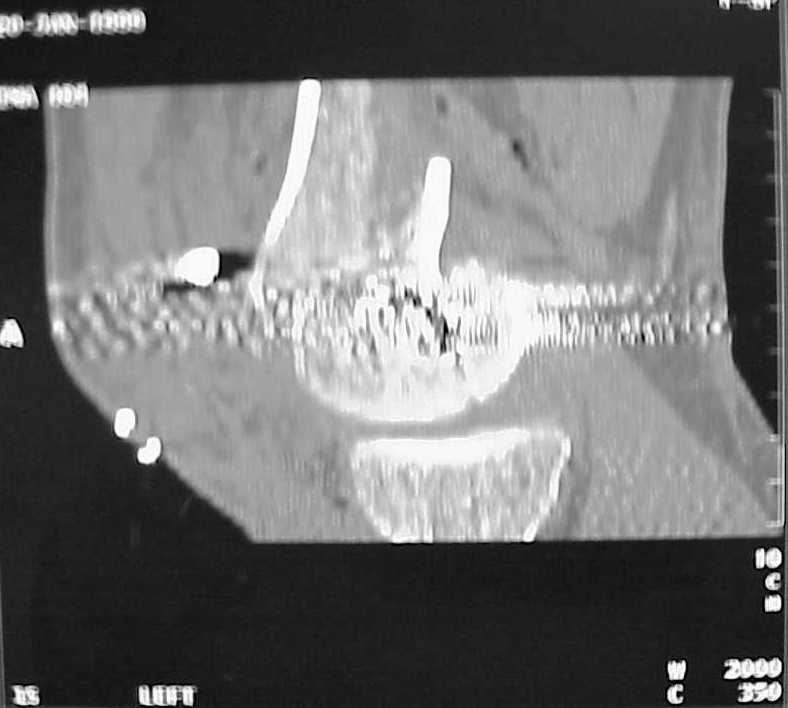

Use 6.5 mm cannulated screws if you have and

place one anterior to where IMN will go if anterior cortex if insufficient and AP screws on either side of the IMN out of the trochlea to provide some additional varus/valgus stability. I worry about the leg going into valgus w/the lack of lateral cortex.

See attached case that was done several years ago before LISS. He had comminuted trochlea and anterior blocking screws were used to prevent anterior IMN cut-out.